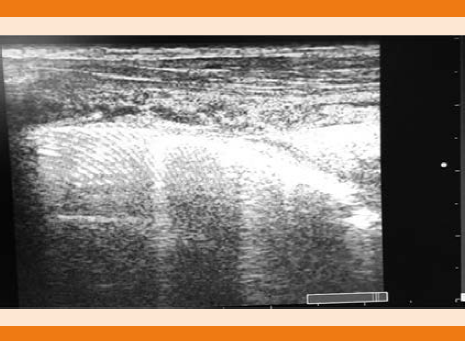

El ultrasonido pulmonar reveló más de tres líneas B (Figura 1), signo de hepatización pulmonar, así como derrame pleural escaso en el pulmón derecho, sugerentes de área de consolidación compatible con neumonía lobar derecha.